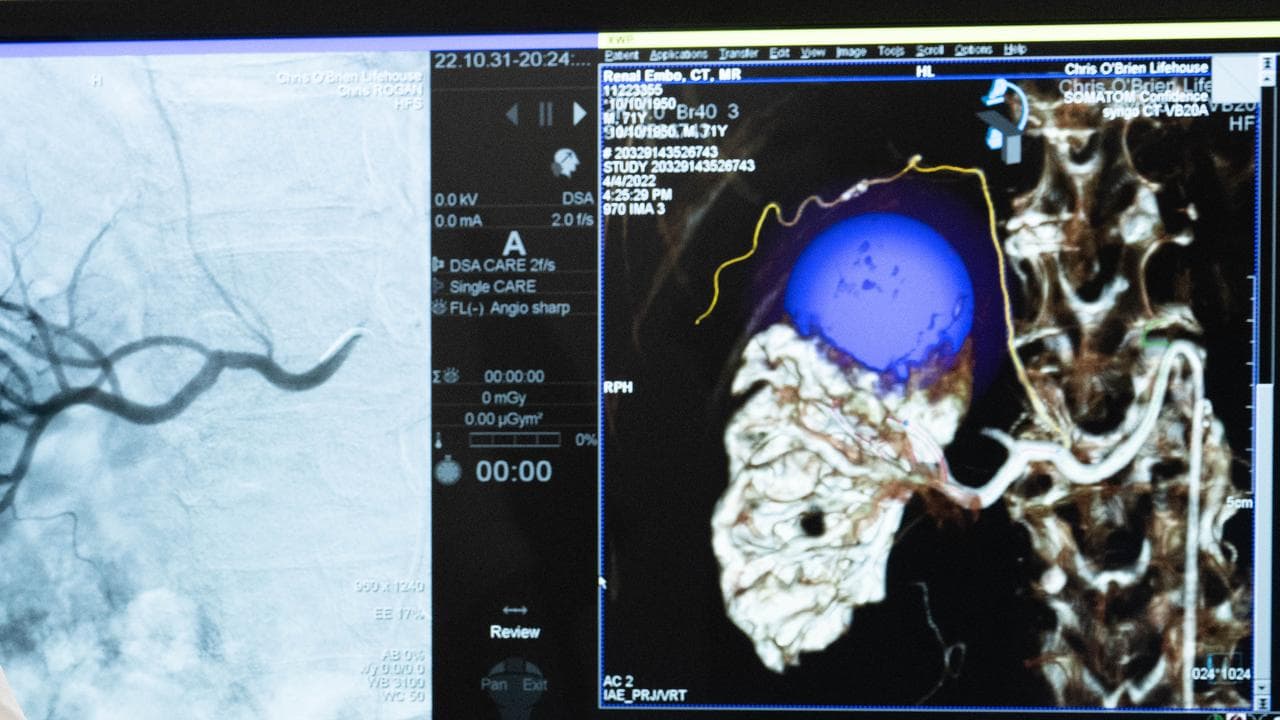

Ovarian cancer did not offer a single pathway of treatment and each patient needed to be catered to individually, Chris O’Brien Lifehouse medical oncologist Michelle Harrison said.